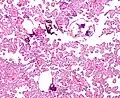

The tumor is neuroectodermal in origin and similar in structure to a normal choroid plexus. They may be created by epithelial cells of the choroid plexus. Papillary fronds lined by bland columnar epithelium are visible under the microscope. Normal absences include mitotic activity, nuclear pleomorphism, and necrosis.[10] Tumors have positive immunohistochemistry for cytokeratin, vimentin, podoplanin, and S-100.[11] Up to 20% of choroid plexus papilloma patients may test positive for glial fibrillary acidic protein (GFAP).[12] Studies have found that fourth ventricle cancers express more S100 than lateral ventricle tumors, and older patients (over 20 years) express more GFAP and transthyretin than younger patients.[13] Some individuals with choroid plexus papilloma have germline TP53 gene mutations, according to genetic analyses.[14] These cancers rarely exhibit nuclear p53 protein positivity. Aicardi syndrome, hypomelanosis of Ito, and 9p duplication are syndromic correlations of choroid plexus papilloma.

Micrograph of a choroid plexus papilloma. H&E stain.

Micrograph of a choroid plexus papilloma. H&E stain. -